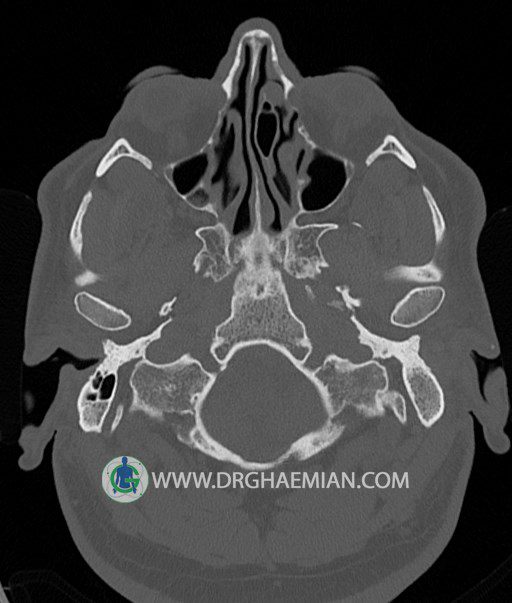

سی تی اسکن گوش داخلی به رادیولوژیست اجازه می دهد تا سطوح مختلف، یا اسلایس هایی از استخوان های که از جمجه به گوش می روند را از طریق امواج ایکس چرخشی مشاهده کند. در این کیس اودیت مدیا، ماستوئیدیت مزمن، اوتیت خارجی، انحراف سپتوم بینی، کونکا بولوزا و افزایش ضخامت سینوس ها مشاهده می شود.

در HRCT از استخوان تمپورال با مقاطع آگزيال ، ساژيتال و کرونال ظريف ( 0.6 mm ) :

– نماي کوکلهآي دو طرف با 2.5 دور گردش مجرا

– نماي semicircular canal خلفي ، لترال ، فوقاني و وستيبول

– استخوانچه هاي گوش داخلي شامل malleus ، incus و stapes (دنسيتي و رديف استخوانچه ها )

– نماي oval window و round window ، tympanic cavity ، attic و کانال گوش داخلي

– انحراف سپتوم مياني بيني به راست

– کونکا بولوزا در کونکاي مياني چپ و

– افزايش ضخامت مخاطي در سينوس هاي اتموئيد و ماگزيلاري